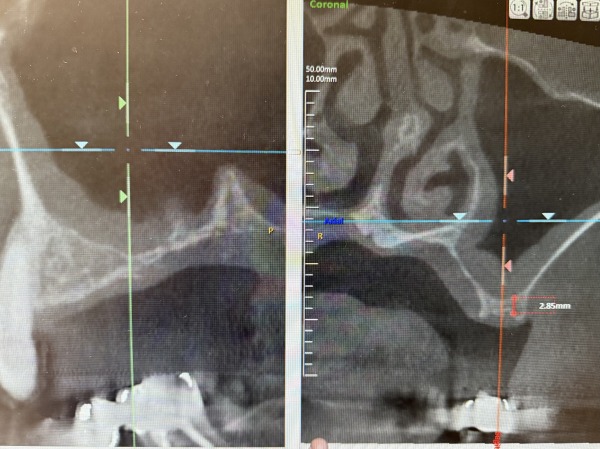

こちらがCTでの診断画像(お顔を横から見ている状態)になります。

左上4番目はある程度の骨量があり、ソケットリフトという方法を用いてインプラント処置が可能と判断できました。

しかし、左上5番目は骨の厚さが3mm弱と薄く、この状態では噛む力に耐えられるインプラントの固定が得られず、サイナスリフト(上顎洞挙上術)という骨を作る特殊な処置を行った後にインプラント治療を行っていくことが必要と診断しました。

こちらがお顔を前から見ている状態の画像になります。インプラントを支える骨が少ないのが分かるかと思います。